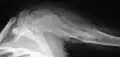

X-ray showing calcified enchondromas localized in finger a 37-year-old patient affected with Ollier disease -

X-ray showing enchondromas localized in the humerus of a 37-year-old patient affected with Ollier disease -